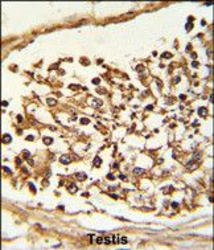

Immunohistochemistry

GTX53804 IHC